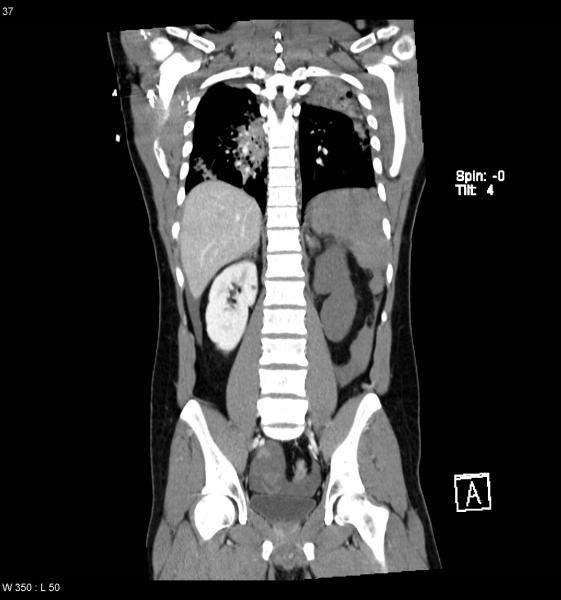

Isquemia mesentérica: Aguda y crónica